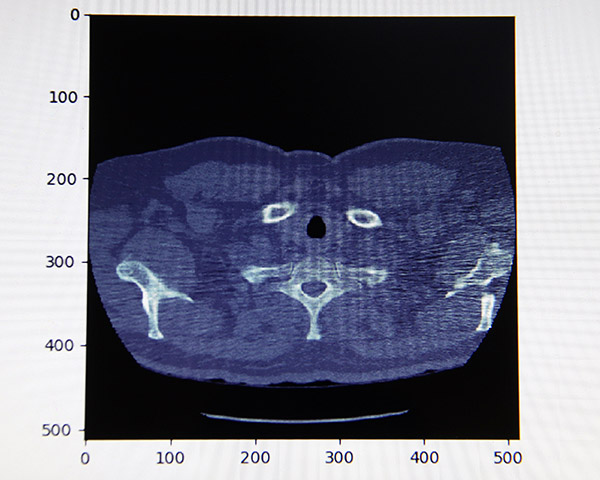

El sistema, creado por Ximena Fernanda Cortés Perales, Isaac Iván Aguirre Bahena y Sergio Martínez Ávila, alumnos de la Escuela Superior de Cómputo (ESCOM), analiza imágenes de tomografías computarizadas del tórax y las clasifica para elaborar un pre-diagnóstico, que puede ayudar a los médicos especialistas en la elaboración de sus diagnósticos concluyentes.

Para el análisis digital de las imágenes, los jóvenes emplean técnicas de reconocimiento de patrones (Redes Neuronales Artificiales), con las que clasifican las imágenes de acuerdo a ciertos patrones, rasgos y características deseadas.

Subrayó que la interpretación de la imagen de una tomografía de tórax no es sencilla por la cantidad de información contenida, lo cual puede dificultar la toma de decisiones y provocar diagnósticos erróneos.